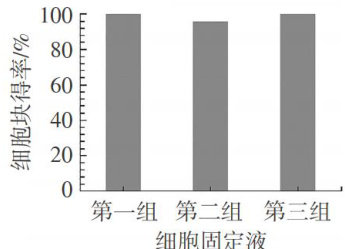

材料科技应用 | 胸腹水细胞蜡块制备与性能测试以及诊断技术应用

材料科技应用 | 胸腹水细胞蜡块制备与性能测试以及诊断技术应用